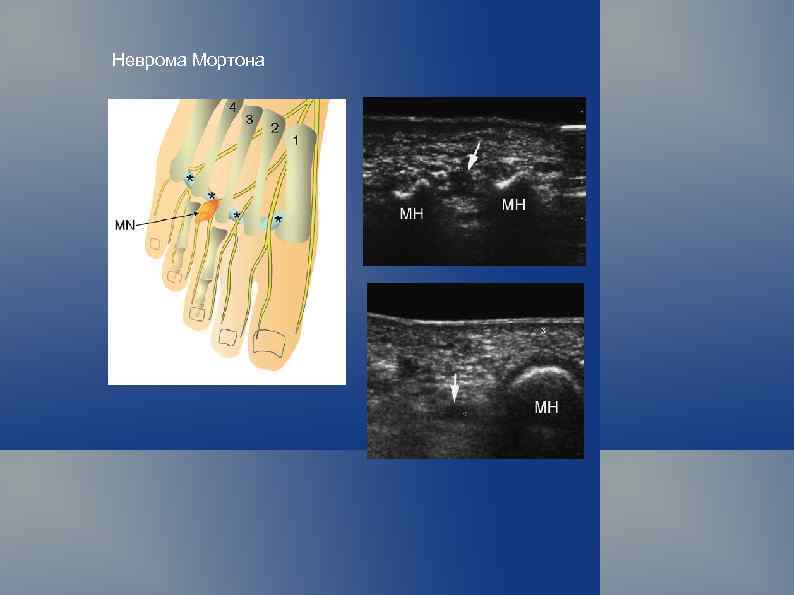

Классификация опухолей мягких тканей (ВОЗ, 1969 г. ) Опухоли мезотелиальной ткани. Доброкачественная мезотелиома. Злокачественная мезотелиома. Опухоли и опухолевидные поражения периферических нервов. Доброкачественные: травматическая неврома; невро-фиброма; неврилемома (шваннома); неврофиброматоз (болезнь Реклингаузена). Злокачественные: злокачественная шваннома (неврогенная саркома, неврофибросаркома);

Неврома Мортона